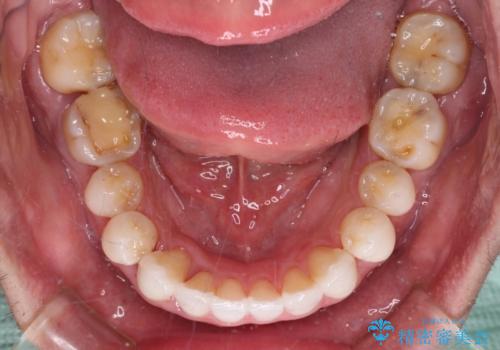

前歯のクロスバイトを改善 インビザラインによる矯正治療

- 前歯のクロスバイトを気にして来院された患者様です。

デコボコやクロスバイトが散見されたため、IPR(歯と歯の間を削る)によってスペースを獲得できるように設計し、インビザラインにより治療を行うこととしました。

今回は、ワイヤー装置を併用することなく治療を行い、トラブルなく、満足のいく歯列に整えることができました。

矯正治療の途中でホームホワイトニングを併用され、術前とは見違えるほどきれいな口元となりました。